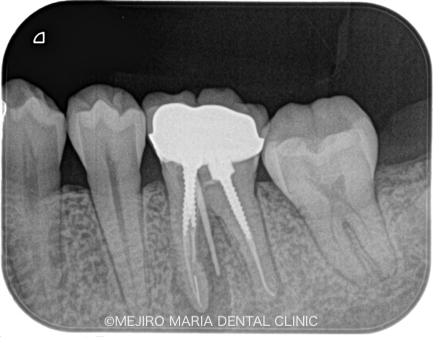

根管治療を2回施し、2回目の治療では、術前に確認されていた瘻孔は消失し、すでに治癒傾向を示していました。

術後3ヶ月で、根尖部に確認されていた黒い透過像(根尖性歯周炎)は明らかな縮小傾向を示していたため、最終補綴(被せ物)の処置を行いました。

今後2年間の経過観察を行い、術後の予後を確認していく予定です。

今回の治療では、大きいスクリュータイプの築造体を除去し、かつ根尖にある破折ファイルを除去したが、レントゲンで分かるのは、健全な歯質をほとんど削らず対処できたことも、今回の症例の重要なポイントであると考えています。

なぜかというと、どんなにコンセプトを守って治療をしたとしても、大きく歯を削り過ぎてはその歯の予知性を低下させてしまうからです。また、ほとんどの再根管治療でのトラブルは、築造体の除去時に大きく削り過ぎたことで、かえって状況を悪くしてしまった症例もよく拝見します。そのため歯科医院を選ぶ際には、設備はもちろんのこと、熟練した技術を伴った歯科医師を選択することを推奨します。